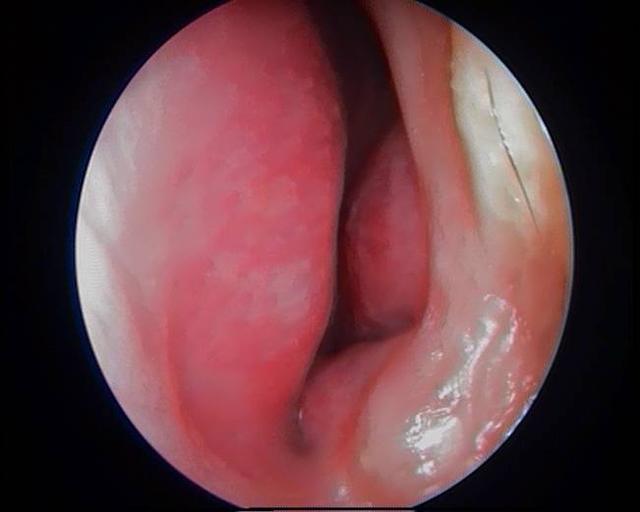

鼻息肉圖片

鼻息肉